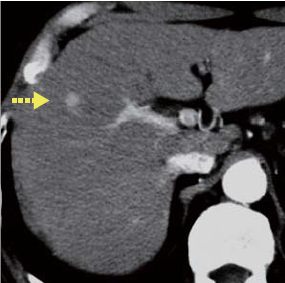

Abdominal CT findings

The tumor in the anterior segment had approximately equal absorption in simple CT, whereas with contrast CT a high-absorption region 1 cm in diameter was found in the arterial phase, and a faint low-absorption region 2 cm in diameter was found in the equilibrium phase

Contrast CT arterial phase

Contrast CT equilibrium phase